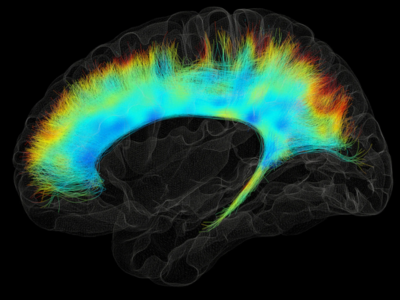

No 1 | Planifier la résection d’une tumeur cérébrale à l’aide des circuits cérébraux

No 2 | La matière blanche classée

No 10 | Tractographie du cervelet